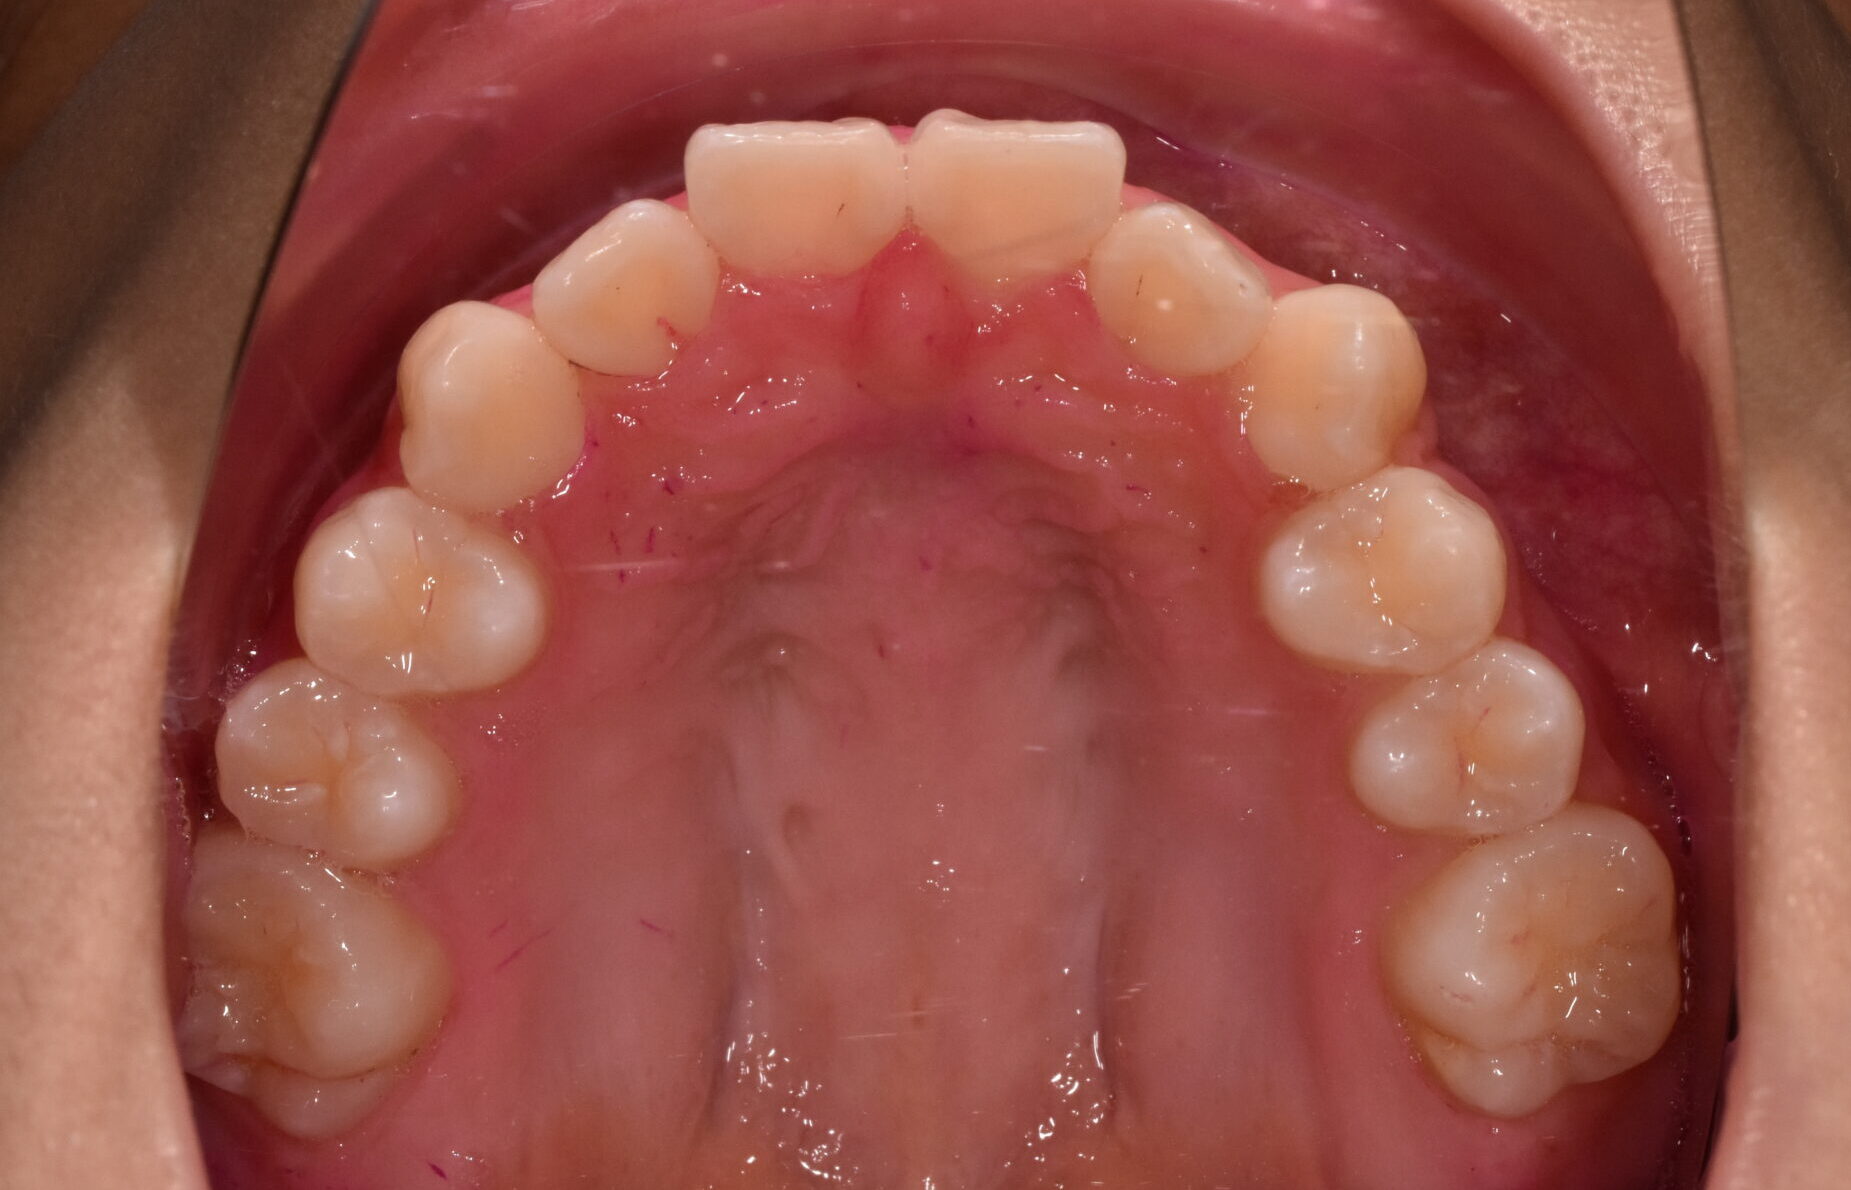

治療前

治療後